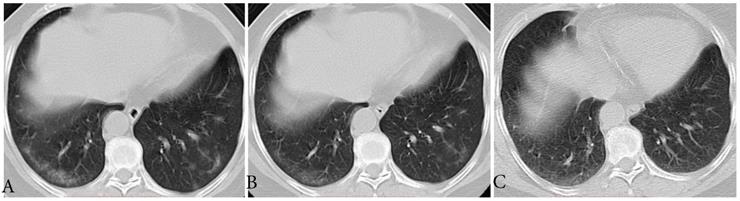

The CT findings of 12 (66.7%) individuals showed type-GI, that is decrease in extent and density from the first to last CT scans (Fig. 1). The median interval time from first CT scans to last CT scans was 7.5 days (range, 3-18). Three of them had mild coughs, and the period from the date of first CT scans to the symptom onset ranged from 2 to 3 days. All of the 12 individuals had RT-PCR conversion with a median interval of 9.5 days (range, 5-19).

Figure 1

Typical evolution of type-GI in a 61-year-old female with asymptomatic SARS-CoV-2 infection. A, Day 0, the first chest CT showed multifocal lesions of subpleural GGO in bilateral lower lobe. B, Day 3, obvious resolution of the first GGO was observed. C, Day 6, continued resolution with minimal residual GGO was observed, the patient had two consecutive negative results of RT-PCR (day 6 and 7). GGO, ground-glass opacity; GI, gradual improvement; SARS-CoV-2, severe acute respiratory syndrome coronavirus 2.